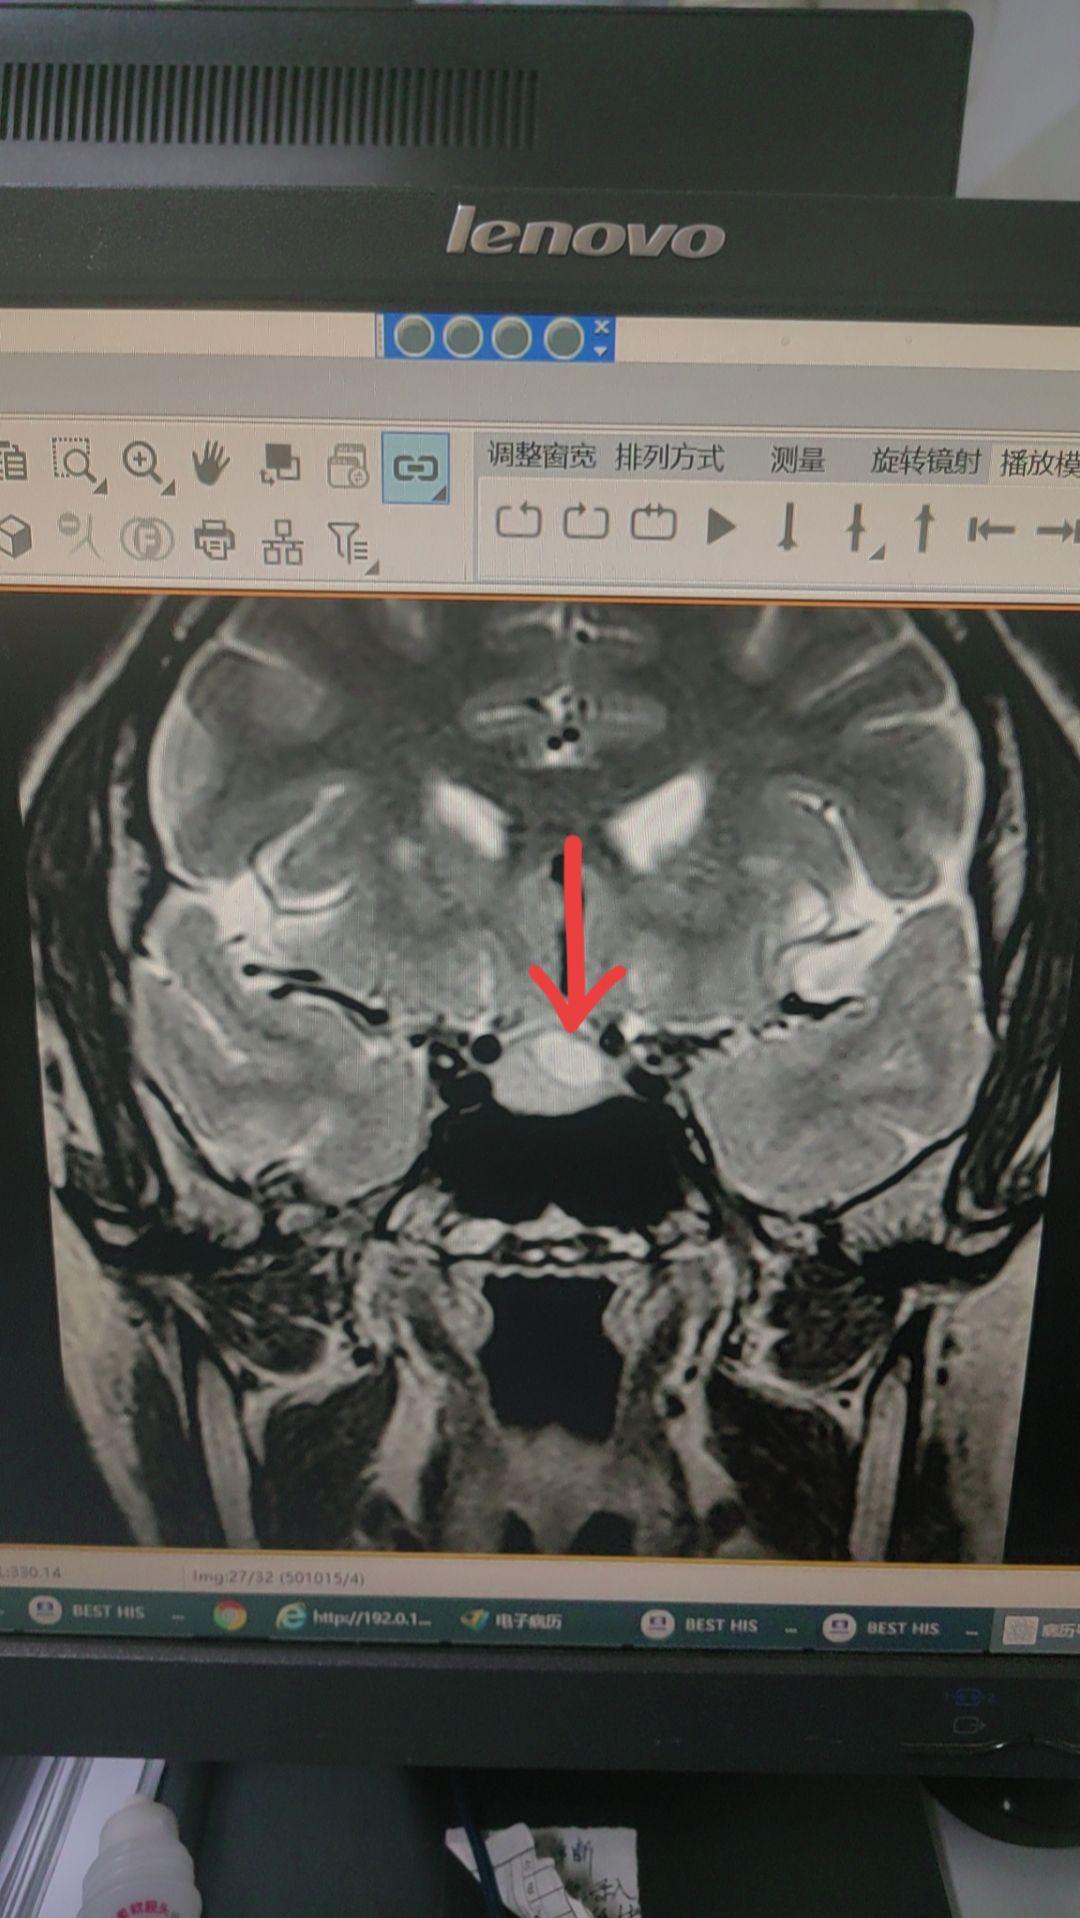

脑垂体瘤